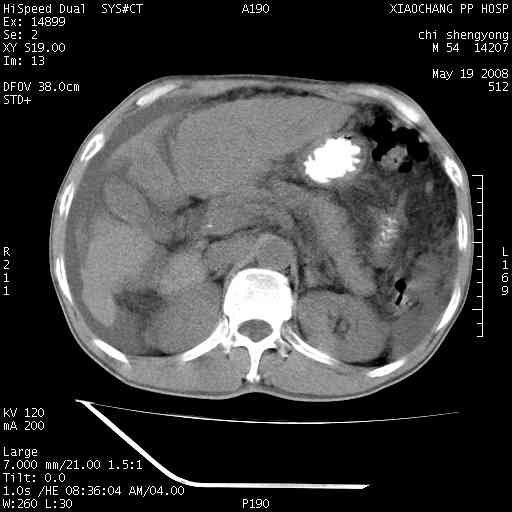

以下是引用zjzjr在2008-5-21 10:52:00的发言:[br]肝左叶巨块型肝癌伴门静脉左支瘤栓形成.肝硬化、腹水,胃底静脉曲张,脾术后改变。

以下是引用随光逐影在2008-5-21 16:20:00的发言:[br]1)肝左叶肝癌伴门静脉左支瘤栓形成,腹膜后淋巴结转移。2)肝硬化、腹水、胃底静脉曲张。3)胆囊炎。4)脾脏缺如,为切除术后所致。